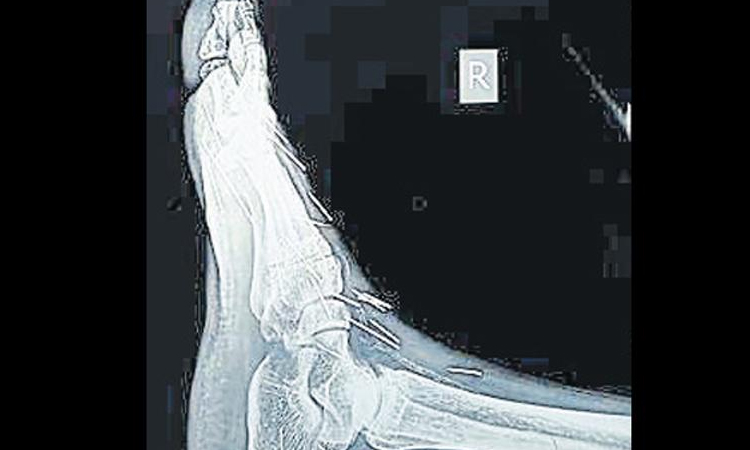

text_fieldsജയ്പൂർ: പിന്നുകൊണ്ട് നിർമിച്ച മനുഷ്യ കുഷ്യൻ എന്നു വിളിക്കാം രാജസ്ഥാൻ സ്വദേശി ബദ്രിലാൽ മീണയെ. 75 പിന്നുകളാണ് 56കാരനായ ബദ്രിലാലിെൻറ ശരീരത്തിൽ നിന്ന് കണ്ടെത്തിയത്. കഴുത്ത്, കൈത്തണ്ട, കാലുകൾ എന്നീ ഭാഗങ്ങളിൽ തൊലിക്കടിയിലായാണ് പിന്നുകൾ കാണപ്പെട്ടത്.

വലതുകാലിലെ വേദനക്കും പ്രമേഹത്തിനും ചികിത്സക്കായി കോട്ടയിലെ സ്വകാര്യ ആശുപത്രിയിൽ സ്കാനിങ്ങ് നടത്തിയപ്പോഴാണ് സംഭവം ശ്രദ്ധയിൽ പെട്ടത്.